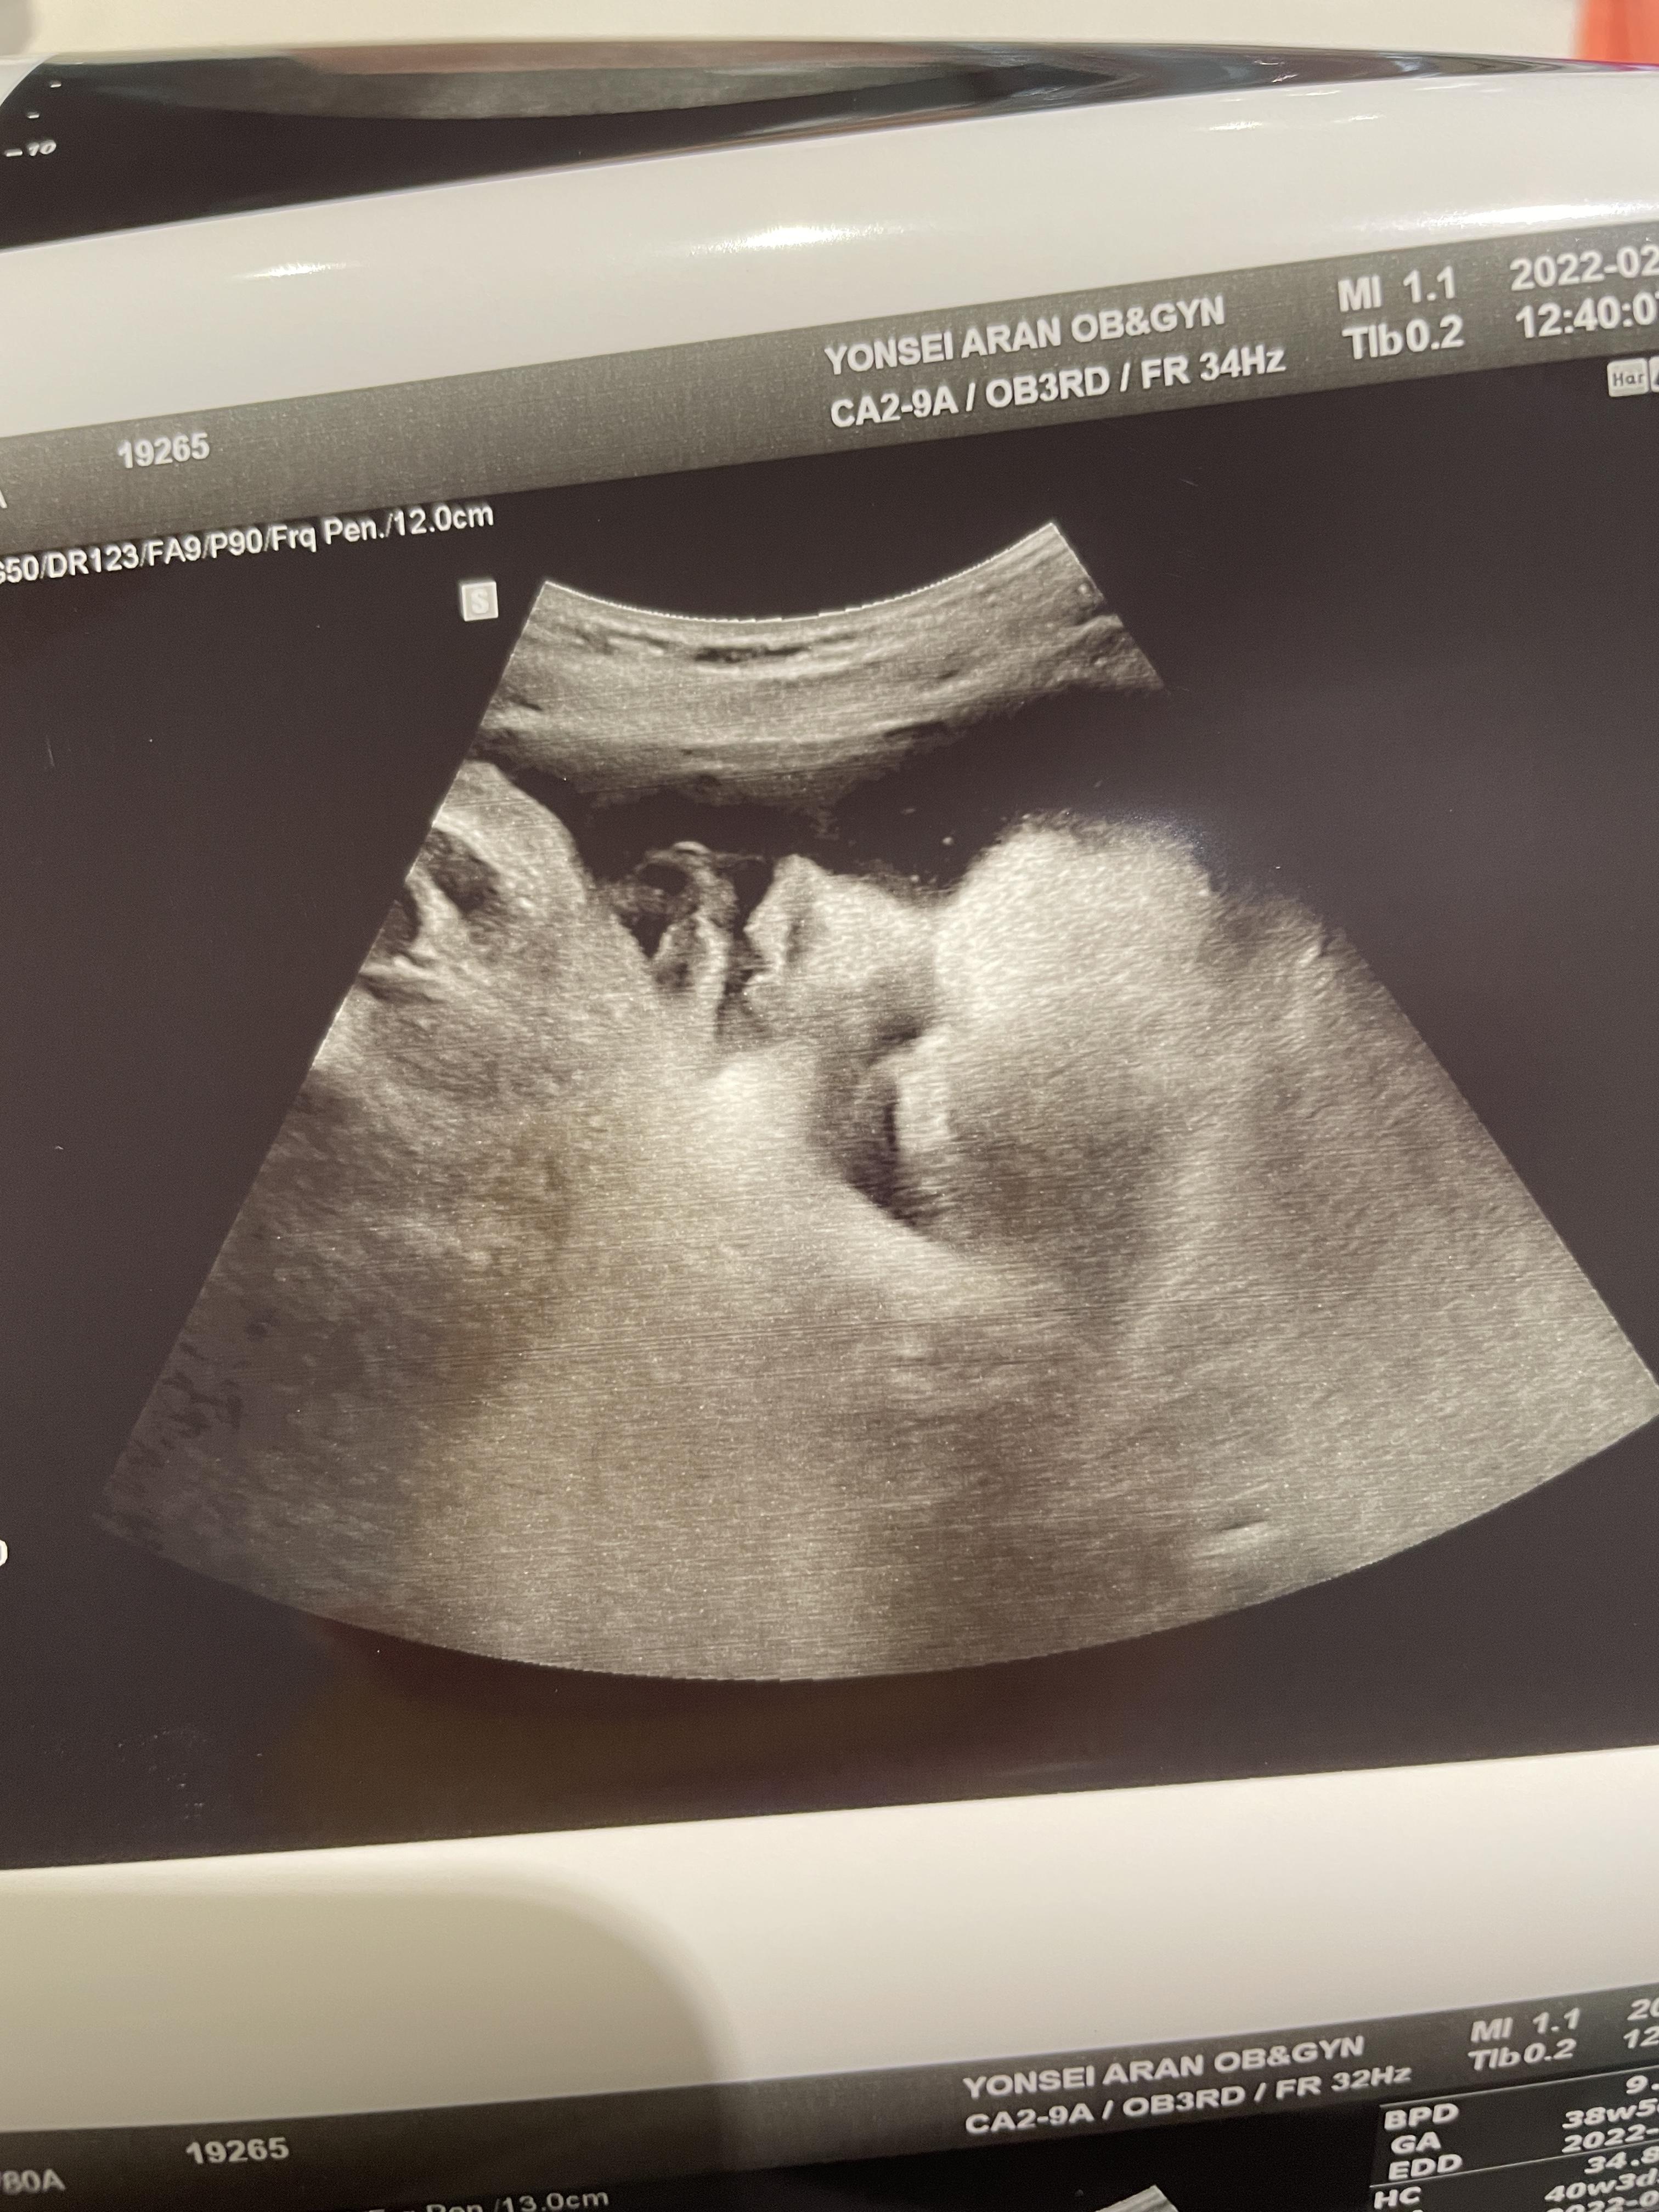

38주 1일차 진료

애기가 얼굴이 너무 잘보인다며 웃으셨다.

하나도 안내려왔다고...ㅠ

그와중에 머리는 역시 커졌고,